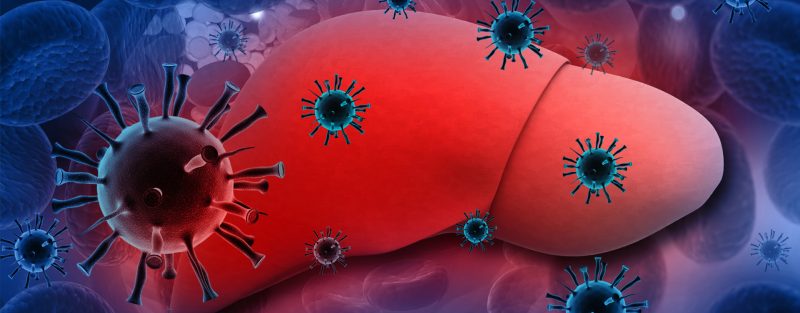

هپاتیت یعنی التهاب کبد و در میان عوام مردم به یرقان و زردی مشهور است. مهمترین عوامل ایجاد کننده آن ویروسها هستند. ویروسها موجودات بسیار ریزی هستند که از فرد آلوده به فرد سالم منتقل می شوند وبرای رشد وتکثیر خودبه یک موجود زنده نیاز دارند.

عفونتهای ویروسی کبد که به عنوان هپاتیت طبقه بندی می شوند عبارتند از: هپاتیت A, B,C,D و E ویروسهای مختلفی مسئول هر یک از انواع این هپاتیتها می باشد. هپاتیت A یک بیماری حاد و کوتاه مدت است در حالی که هپاتیت B ، C و D و به احتمال زیاد مزمن می شوند. هپاتیت E معمولا حاد است اما می تواند به خصوص در زنان باردار خطرناک باشد.